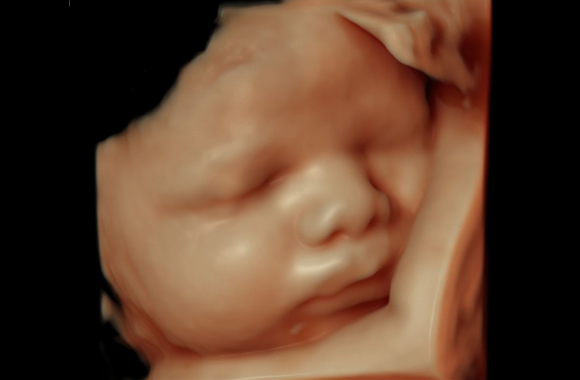

Las ecografías 5 D tienen la particularidad de ser tridimensionales y en movimiento. No obstante, la diferencia que presentan, por ejemplo, con respecto a las llamadas 4D, es que permiten ver mucho mejor las sombras que se pueden generar en el rostro del feto.

Pero no solo eso, además, tienen una mayor resolución por lo que la imagen que se ve es mucho más clara y más “verdadera”. Es decir, una ecografía 5D es mucho más realque cualquier otra de las que existían hasta ahora.

El hecho de que sean más nítidas y tengan más resolución trae consigo que contribuyan mucho más que ninguna a poder detectar anomalías o malformaciones en el feto. Al ser así, eso permite que, por tanto, se pueda establecer un tratamiento cuanto antes en los que sea necesario y oportuno.

Ayudan enormemente a realizar las mediciones del cuerpo del pequeño de una forma mucho más precisa. Así, se podrá conocer mejor si está creciendo y desarrollándose como le corresponde a su edad. De la misma manera, es necesario ser consciente de que permiten percibir mejor los flujos sanguíneos.